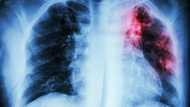

Kungiyar mai sunan Stop TB Partnership STP, ta kuma ce akalla mutane miliyan 1.4 za su rasa rayukansu sanadiyar cutar ta tarin fuka nan da tsawon shekaru biyar.